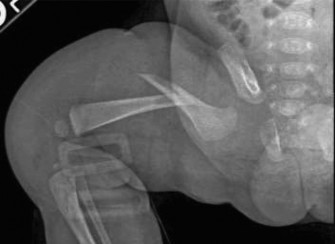

CASE 47 The patient is a 74-year-old man involved in a motor vehicle collision …